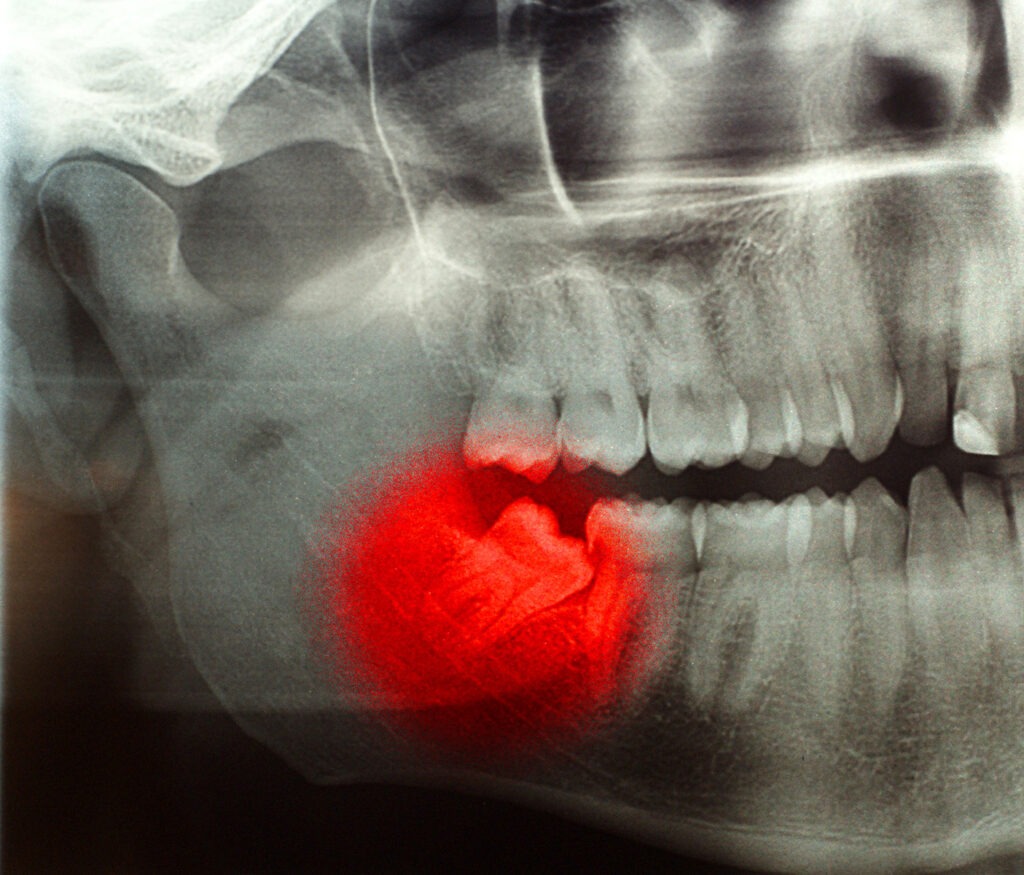

“I had an exceptional experience with Dr. Payam Haghighi! As an initial matter, the office was modern and immaculate, and the staff was friendly and extraordinarily helpful. What stood out to me was Dr. Haghighi’s extensive knowledge and ability to lay things out in plain English. He took the time to explain the reasons underlying my treatment plan, which provided me with extra comfort in what is inherently an uncomfortable situation. And my situation was particularly uncomfortable, as the reason for my visit was a sudden, unexpected throbbing tooth. If understanding the “why” matters to you, I highly recommend Dr. Haghighi. You’ll receive top-notch care from an expert dentist.”